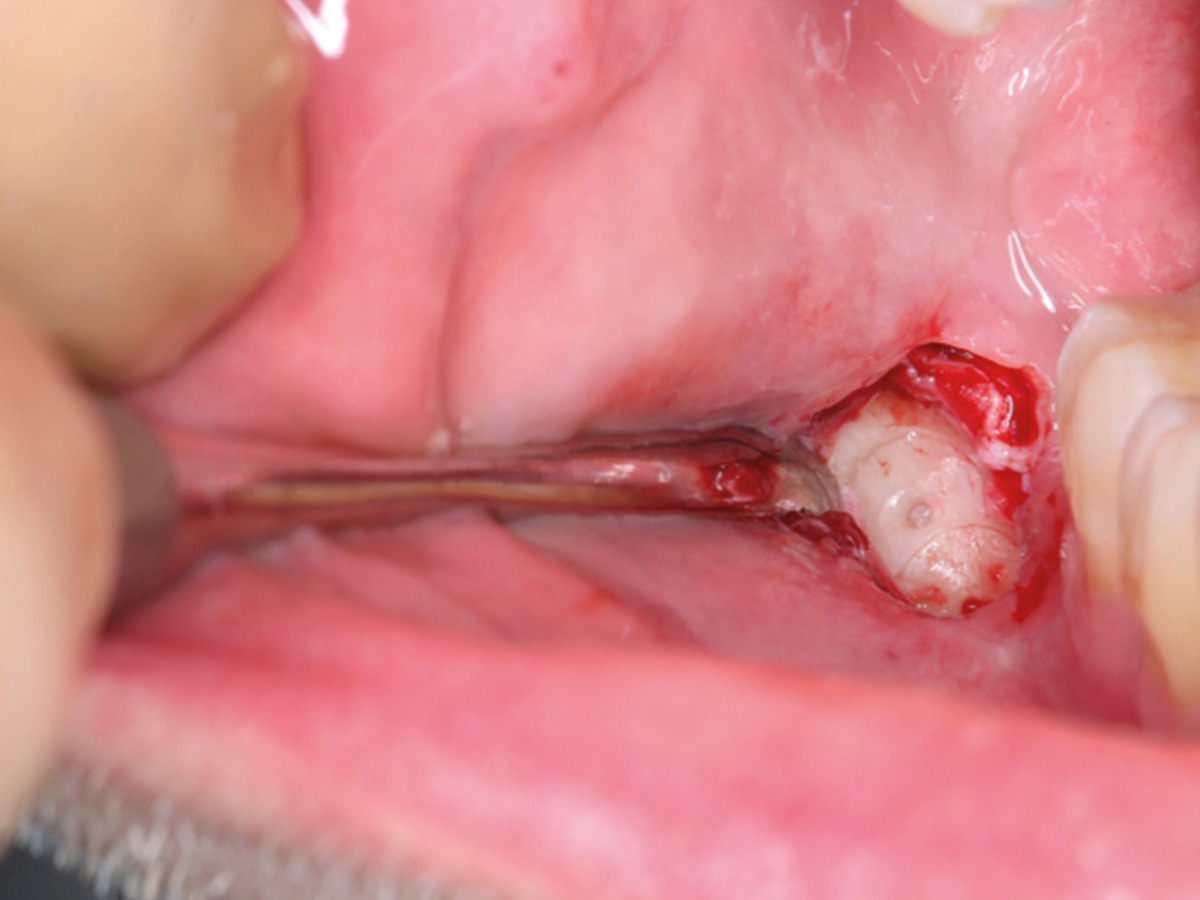

Abbildung 3

Leere Alveole nach atraumatischer Extraktion.